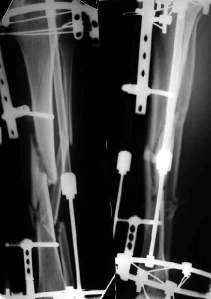

Уважаемые коллеги! На консультации больной предъявляет жалобы на хромоту (укорочение - 2см), боль в месте перелома при нагрузке (спортсмен).

Семь месяцев назад получил закрытый перелом, лечился консервативно в одной из больниц города. Как-бы кто лечил? Сам склоняюсь к LCP с костной пластикой.

При невозможности или чрезмерной травматичности одномоментного восстановления длины можно пойти двухэтапно (аппарат, потом гвоздь). Похожий пример см. тут. Прошло уже года полтора после остеосинтеза. Может, коллега Зырянов покажет годичный результат, если есть?

Александр Николаевич, к сожалению больной не является на контрольные осмотры. Я последний раз видел больного, когда прошло 7 месяцев после операции БОС. У него все хорошо. Каких либо жалоб и ограничений в нагрузке нет. Высылаю снимки до операции и последние снимки.